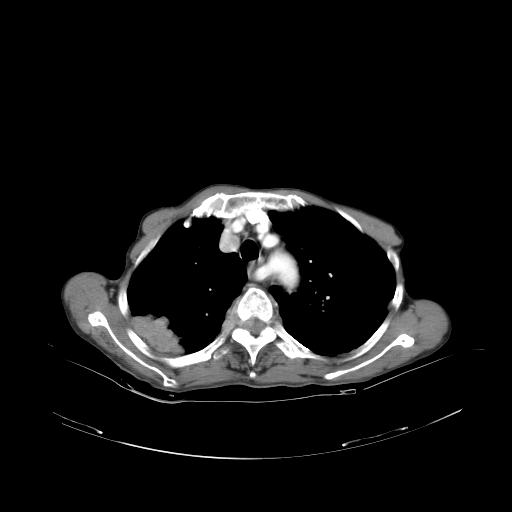

女,72岁,咳嗽一周余,突发右下肢无力二天。

pe:bp-140、80mmhg,精神可,伸舌居中,右上肢肌力正常,右下肢肌力0级,巴氏征+

来院做头颅+胸部ct平扫

遂加作增强:

胸部病变平扫35hu,增强强化至70hu

这个病人首先是胸部病变的定位到底是肺内还是肺外。仔细观察块影位于胸膜下,与胸膜间有透亮带,且近端血管未见明显推移而是引流样改变,形态分叶,说明这个病灶位于肺内胸膜下。很可能是腺癌,腺癌最易致颅内高密度转移灶。局部胸膜有侵犯。

本例颅内见多发大小不等高密度灶,有强化及水肿;另外,胸锁关节层面可能是第四胸椎及右侧肋骨起始部骨质欠连续,椎旁软组织肿胀,建议调骨窗观察。

诊断:右下肺癌伴颅内、胸椎、肋骨转移可能性最大。